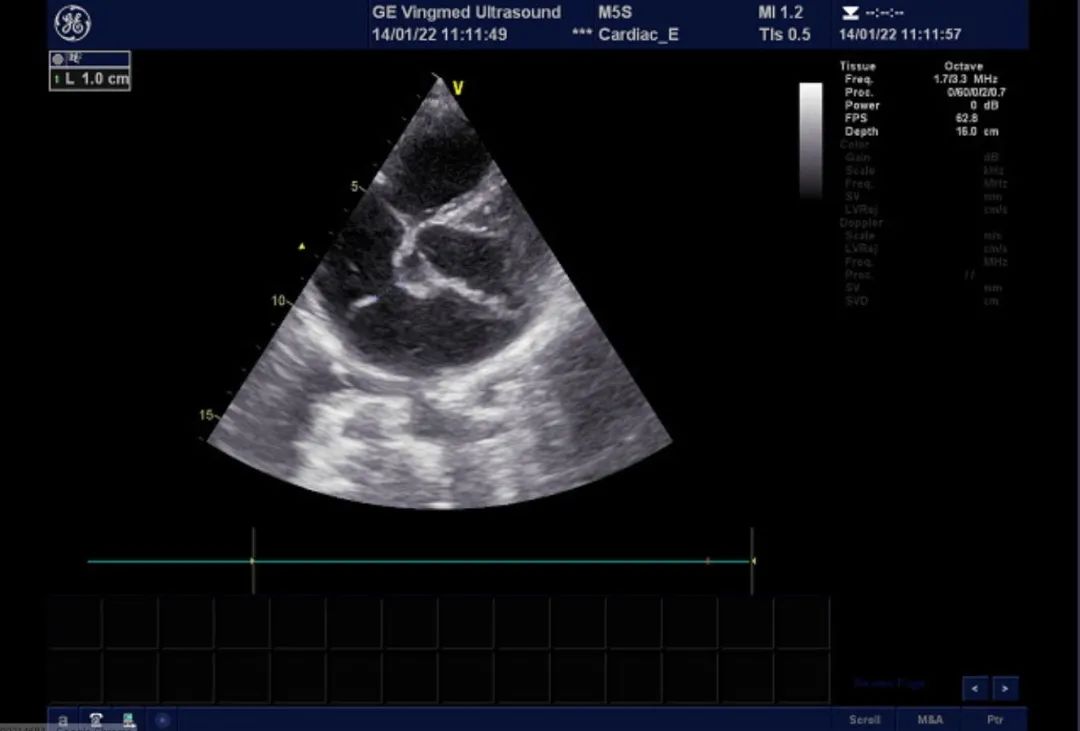

心脏超声:AO:26mm, IVSd: 8mm, LVDd:44mm, FS:43%,HR:84BPM LA:39mm, LVPWd:8mm, LVDs:25mm, LVEF:74%,RV:36mm M型、2-DE:左房饱满,大小约45*55mm,左室大小正常范围,右心增大,右房大小约44*51mm,升主动脉不宽,主波明显,重搏波清晰,主瓣清晰,启闭无殊;二尖瓣增粗、增强,后叶收缩期凸向左房,P2区为主。室壁不厚,室间隔与左室后壁逆向运动。肺动脉主干内径21mm。静息状态下各切面未见室壁节段性运动异常。房间隔可见两处回声中段,孔1位于近十字交叉处,宽约11mm,十字交叉残端不明显。孔2位于房间隔中段,宽约9mm。三尖瓣瓣环内径约38mm。超声诊断先天性心脏病,房间隔缺损(继发孔型,双孔型考虑),二尖瓣后叶脱垂伴关闭不全(P2区为主,中重度)。

二尖瓣后叶脱垂,大量返流

双孔型房缺,分别为1cm及8mm大